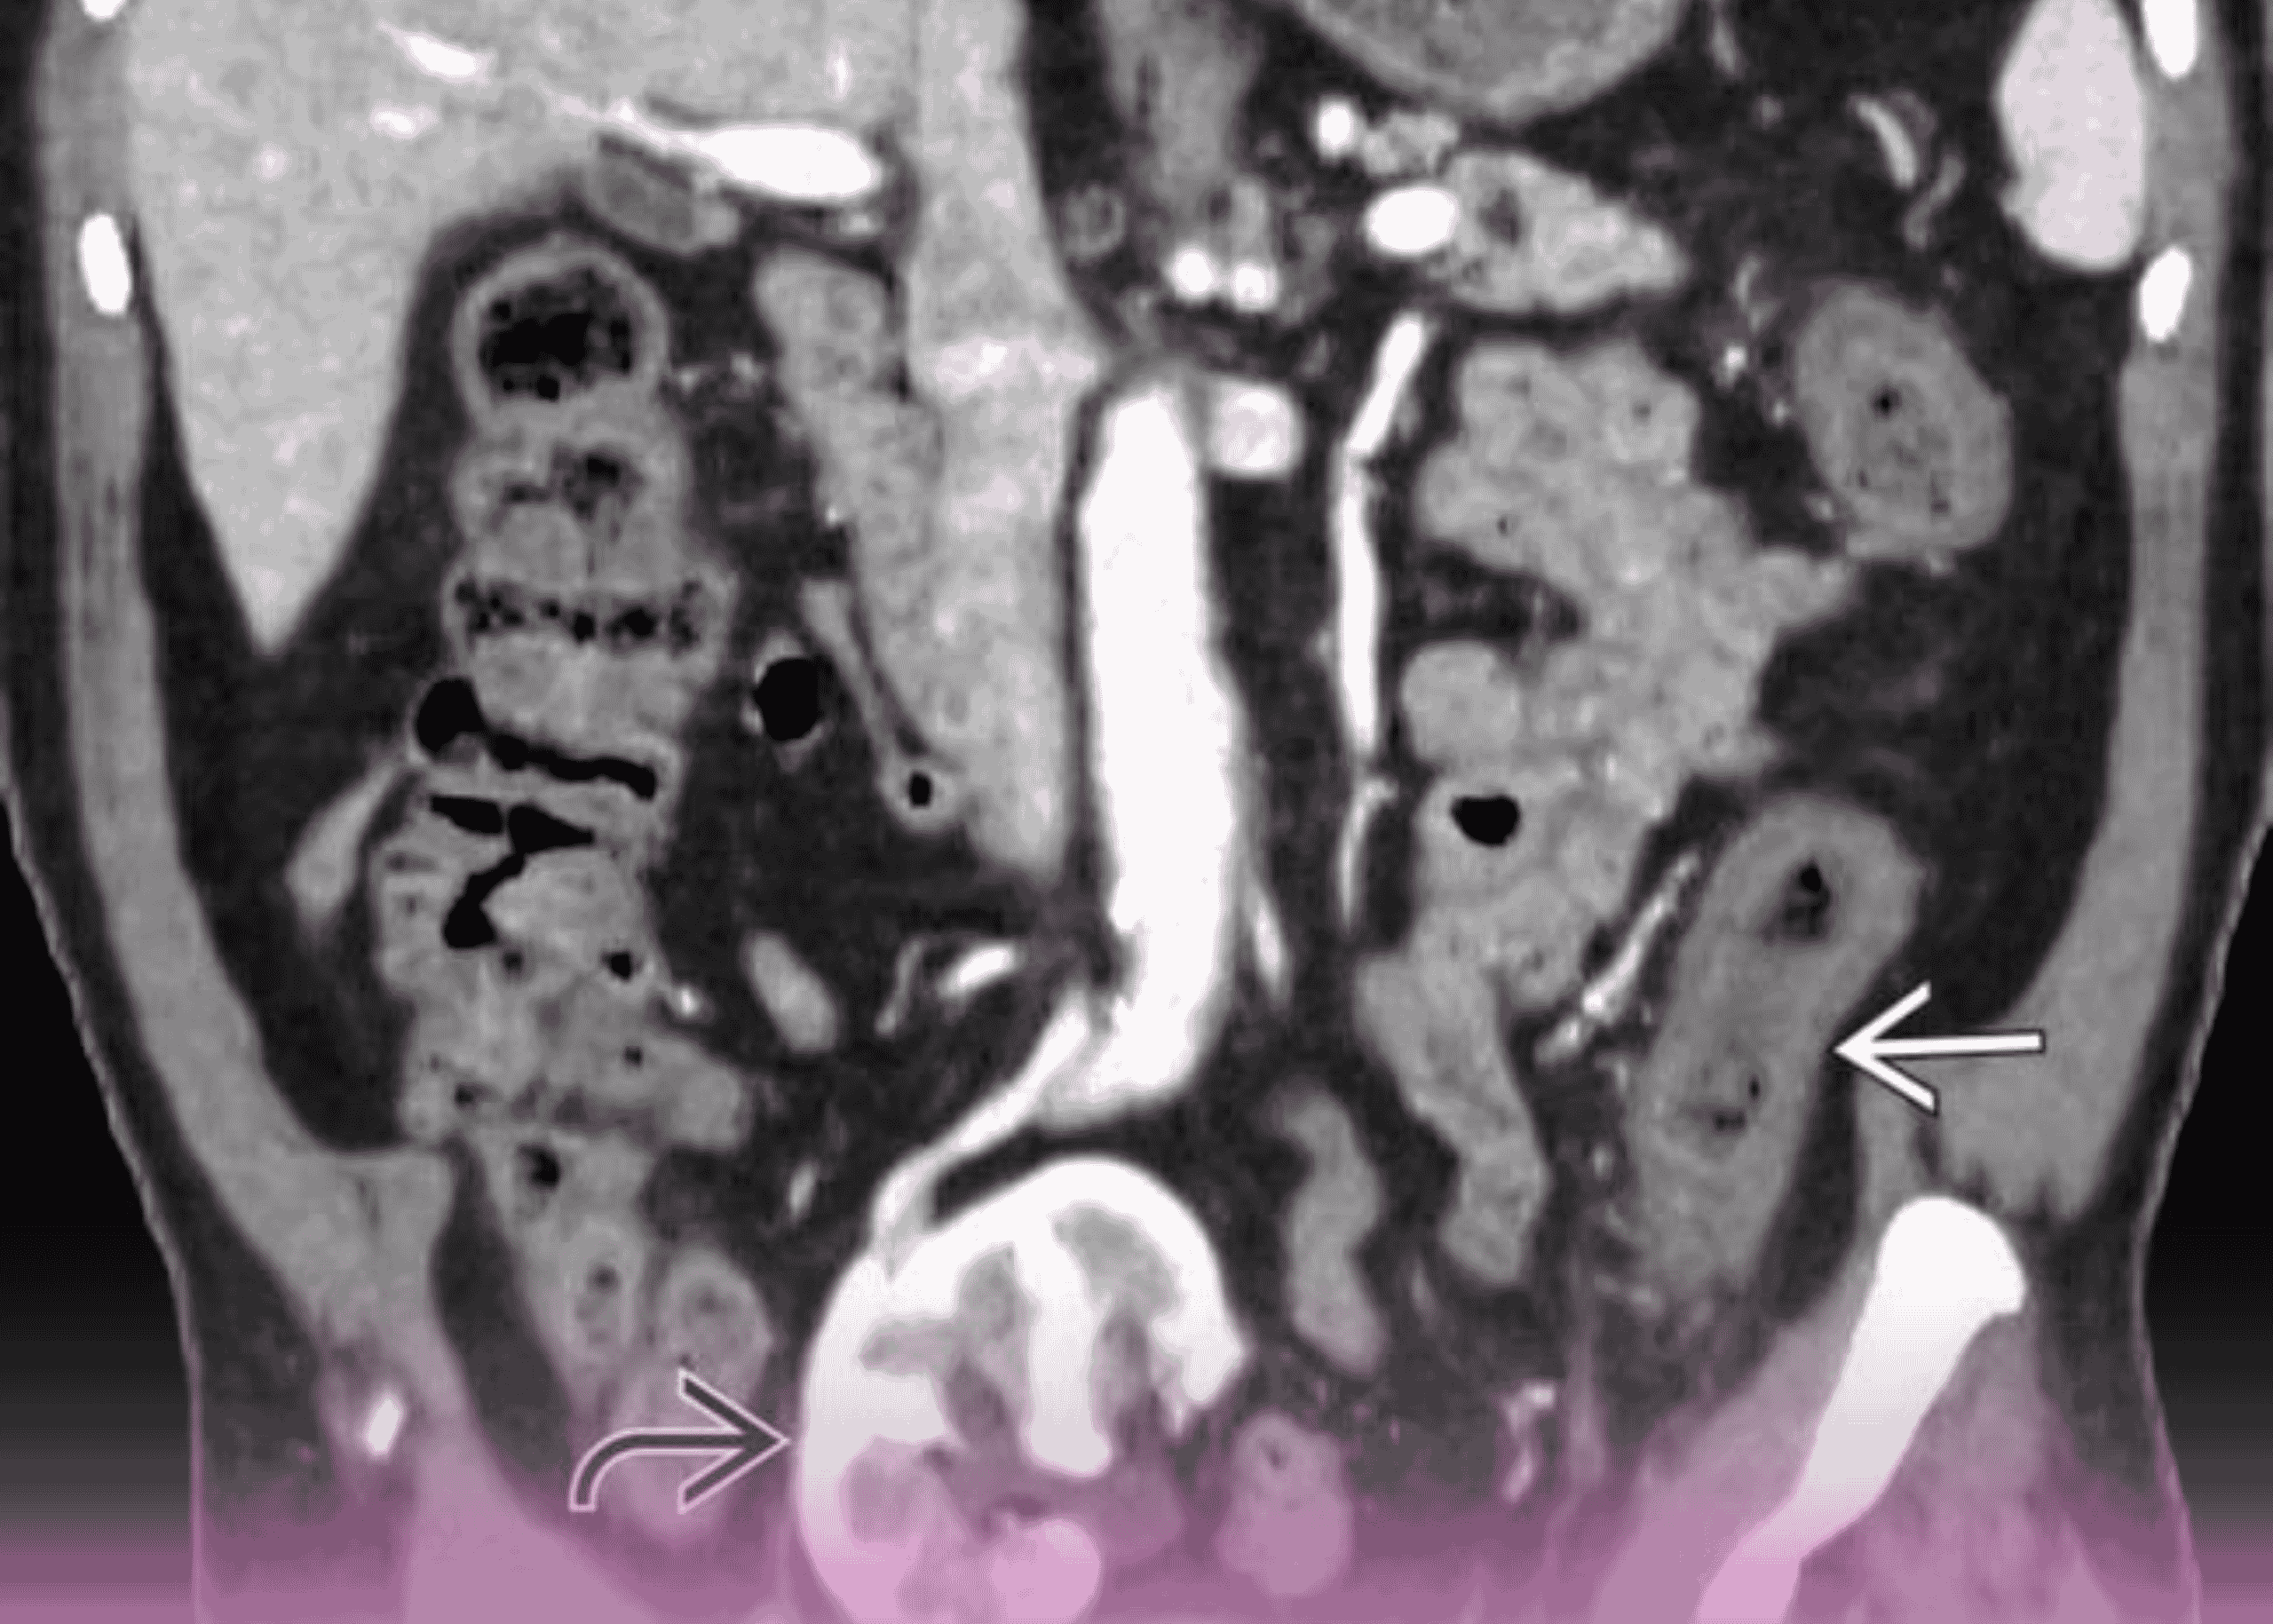

التهاب القولون الإقفاري مع ثقوب متعددة: التدبير الجراحي لحالة مهددة للحياة

مقدمة التهاب القولون الإقفاري يمثل تحدياً كبيراً في جراحة الجهاز الهضمي، خاصة